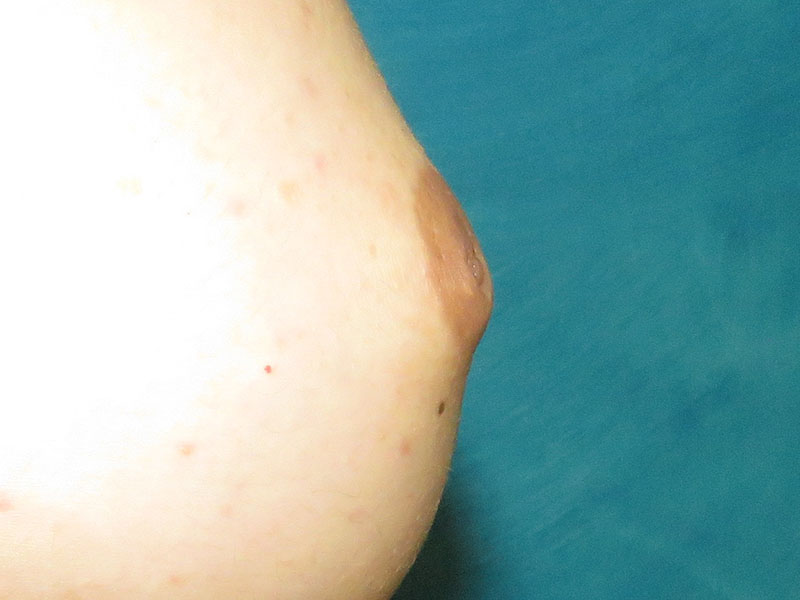

Before and after bilateral inverted nipple correction in a 33 year old woman. She had not had children yet and was relieved to hear that future breastfeeding should still be possible. We take a conservative approach when patients are nulliparous (have never been pregnant) and realize that situations and preferences about having a baby can change with time, so we always preserve a robust connection of milk ducts to the nipple as best we can.

Her nipples were graded as Grade II-III. Grade I inversion means they can self-correct with a pinch or stimulation – they have a slit in the center when they are relaxed but they will come out fully after a pinch. Grade II inversion means the nipples have some degree of nipple protrusion with stimulation but they cannot fully come out. Grade III inversion means the nipples are completely buried and they have minimal correction with nipple pinching, similar to a deep crater.

Follow up photos are shown one month after surgery. This patient had fairly large nipples that formerly were buried, but are now evident! The irregular texture of the nipple glands will gradually become less projecting and less rough as they are exposed to normal exposure to clothing and bras. She started to regain her sensation in two weeks. It often takes several weeks to months for nerves to start to wake up. We have been promised an update about breastfeeding ability when that happens in the future!